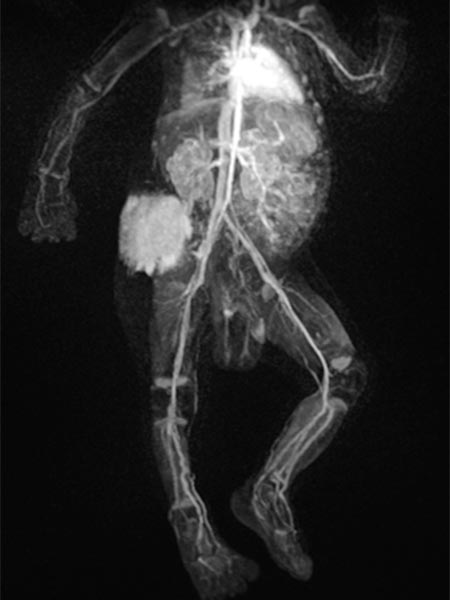

In the final control angiography with long series after injection into the right common iliac artery, the tumor is completely devascularized. The unaffected, physiological arterial branches of the surrounding tissue are all preserved. Thus, the tumor is completely eliminated from the circulation. Activation of coagulation and consumption of platelets in the tumor has stopped.